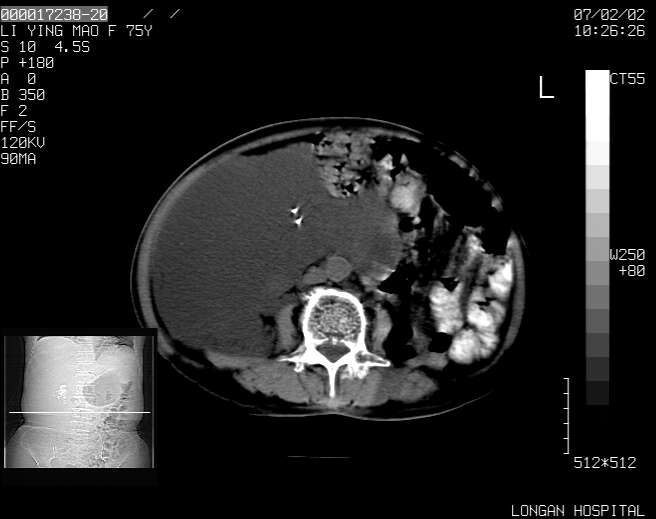

以下是引用dyqct在2007-2-10 8:53:00的发言:[br]考虑:1、肝脏多发囊肿[br] 2、左肾囊肿,右肾多发结石并积水。[br] 3、右胸少量积液。[br] 4、右肾周包裹性积液或淋巴管瘤(有见缝就钻的征象、薄隔、小结节状钙化)?[br] 5、腰椎动脉瘤样骨囊肿?[br] [br] [br]